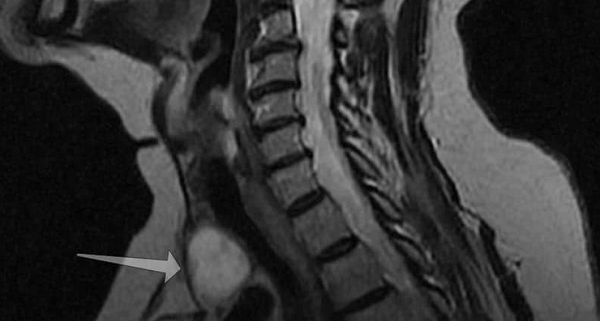

Новообразование (указано стрелкой) на МРТ щитовидной железы

Тиреоидиты - воспалительные процессы, имеют инфекционную и аутоиммунную природу. Вторые встречаются чаще и протекают в хронической форме. Симптомы отсутствуют, в некоторых случаях наблюдается незначительное увеличение органа. При развитии гипотиреоза развивается клиническая картина, характерная для дефицита гормонов щитовидки. Среди врожденных аномалий выделяют: